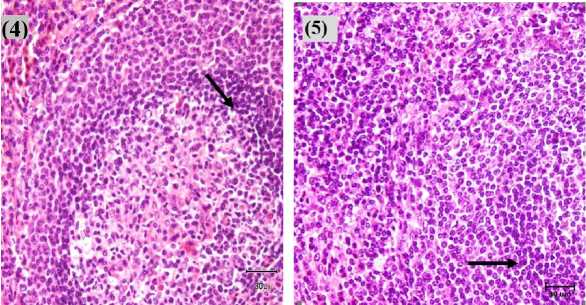

| Hasil | pemeriksaan | mikroskopis |

jaringan limpa, ditemukan adanya perubahan berupa deplesi sel-sel limfoid pada sapi no. 1 yang terlihat adanya peluruhan sel-sel limfoid. Sedangkan jaringan limpa pada sapi no. 2, 3, 4, dan 5 mengalami perubahan berupa proliferasi sel-sel limfoid. Deferensiasi dan pembelahan sel yang mengalami peningkatan, dimana pada pulpa putih terlihat adanya dominasi sel limfosit T. Menurut Darlina et al. (2012) menyatakan limfosit yang mengalami stimulasi akan terjadi perubahan biokimia maupun

diameter sel bertambah, kromatin sel blast menjadi longgar dan terwarnai pucat. Perubahan histopatologi limpa pada Tab. 2 dan gambarnya disajikan pada Gambar 1.

Gambar 1. Struktur limpa sapi TPA, ditemukan adanya perubahan deplesi sel limfoid (tanda panah kuning) dan adanya proliferasi sel-sel limfoid (tanda panah hitam) pada sapi 1, 2, 3, 4 dan 5 (400X, HE)

Struktur histologi limpa sapi bali tersusun atas kapsula, pulpa putih dan pulpa merah (Setiasih et al., 2011). Hasil pemeriksaan 5 sampel limpa sapi bali ditemukan adanya perubahan histopatologi berupa deplesi dan proliferasi sel-sel limfoid. Berkaitan dengan toksisitas logam berat Pb, banyak studi menyatakan kerusakan sel erat kaitannya dengan stres oksidatif dan mekanisme ion. Monisha et al., (2014) menyatakan bahwa stres oksidatif pada sel terjadi apabila terdapat radikal bebas yang tinggi. Radikal bebas dalam hal ini ion Pb akan terjadi reaksi dengan antioksidan yang menyebabkan peningkatan produksi Reactive Oxygen Species (ROS) seperti hydroxyl radical